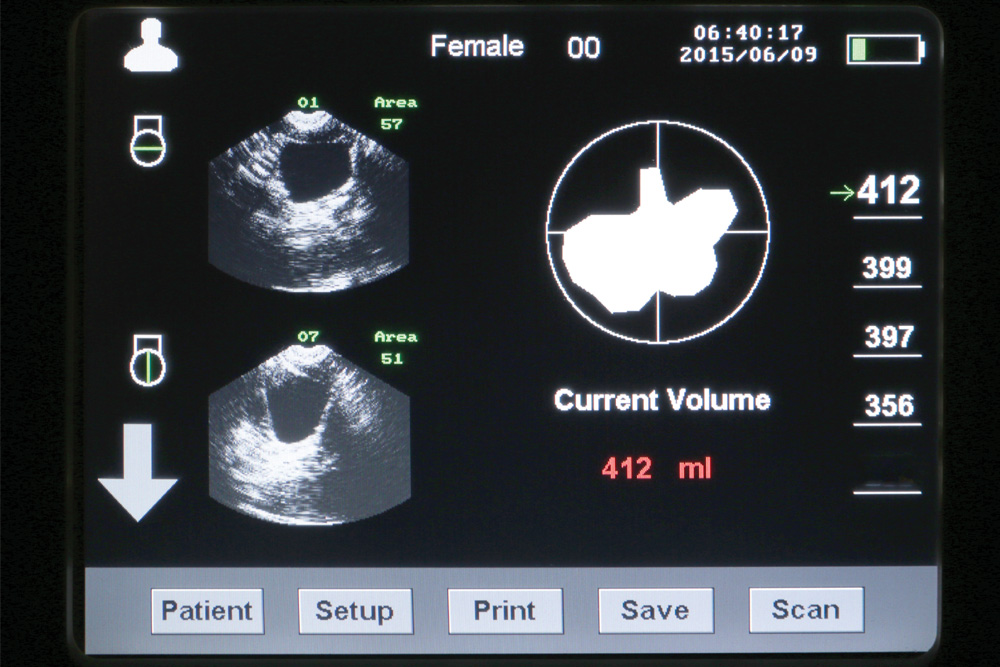

Clear User Interface

Look for a unit with a simple user interface. Units that have large, easy-to-read numbers and less extra data tend to be easier for staff to interpret.